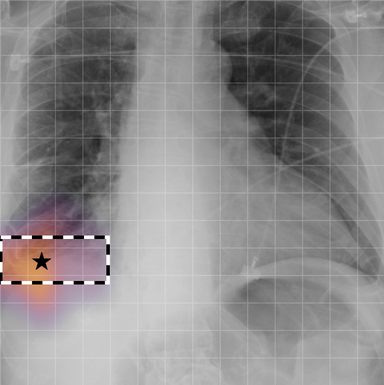

In Figure A.3, we show examples of self-attention rollout [1] maps for pleural effusion and consolidation, including radiologist-annotated bounding boxes surrounding the corresponding pathology in each prior and current image.

To model the attention flow through the transformer encoder block, we first average each attention weight matrix across all heads, subsequently we multiply the matrices between every two layers. For every block we add the identity matrix in order to model the residual connections. Last, we only keep the top 10 of attention weights per block to reduce noise in the final rollout map. In contrast to [21], we do not visualize the rollout map with respect to a [CLS] token. Instead, we choose a reference image patch from the center of the radiologist-annotated bounding boxes, marked with in Figure A.3.

We find that the rollout maps in Figure A.3 are in good agreement with radiologist-annotated bounding boxes, i.e., the reference patch attends to other patches within the bounding boxes in the prior and current image. In addition, we find that BioViL-T is robust to pose variations, e.g., in Figure A.3 (a) we show that despite the vertical shift between prior and current image, the reference patch attends to the correct image patches in the prior image.